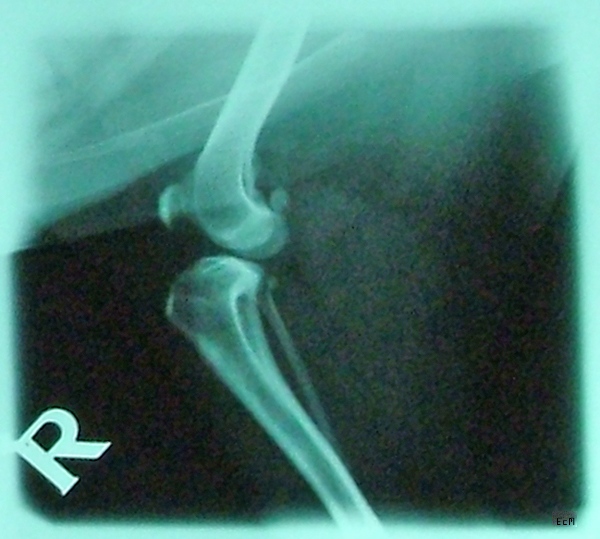

X-ray images of Charlie's leg. 2007